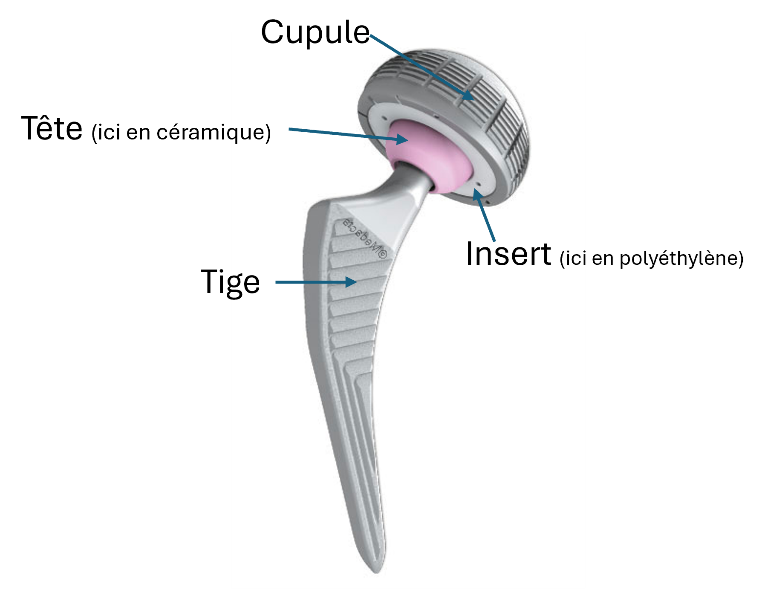

Une PTH remplace les surfaces articulaires usées :

- Cupule + insert côté bassin.

- Tige + tête côté fémur.

On distingue :

- Les pièces fixes : tige et cupule.

- Les pièces mobiles : tête et insert.

La tête de la PTH est soit en céramique soit en métal.

L’insert de la cupule est soit en polyéthylène soit en céramique.

Les matériaux utilisés pour les pièce fixes encrées dans l’os varient selon la nature de la fixation : cimentée ou non cimentée.

Actuellement la plupart des tiges et cupules non cimentées sont en alliage de titane souvent revêtu d’une couche d’hydroxyapatite (sur le schéma ci-dessus aspect gris-mat de la tige).